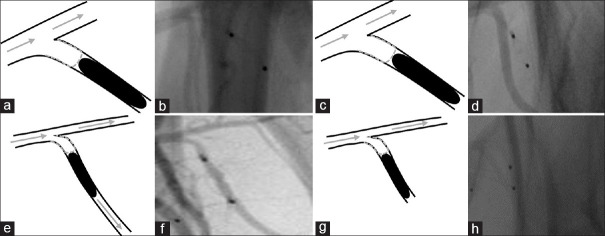

Materials and methods: For aneurysm creation in external carotid and subclavian arteries, Amplatzer vascular plugs were used as occlusion devices, leaving simple stumps that serve as surrogate aneurysms. If necessary and anatomically possible, additional embolic materials, such as coils and liquid embolic agents were used.

Results: We created 42 aneurysms. Aneurysm creation was possible without complications in all cases. There was no spontaneous thrombosis of fabricated aneurysms. Complete perfusion arrest behind the fabricated aneurysm was challenging but achieved in 45% of cases. We were not able to identify significant factors that have an impact on the persisting perfusion of fabricated aneurysms on final imaging, particularly not the presence of side branches in the aneurysm lumen (P = 0.734) or volumes of the fabricated aneurysms (P = 0.620). Albeit not significant, the use of additional occlusive measures (coils, liquid embolic agents) and antithrombotic drugs (ASA, heparin and tirofiban) may be factors for persisting perfusion: Perfusion arrest behind the fabricated aneurysm was twice as high in animals treated with ASA and heparin compared to animals treated with ASA, heparin, and tirofiban (48% vs. 22%; P = 0.149).